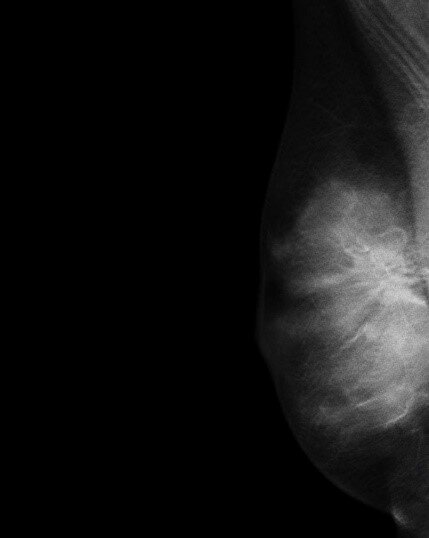

При пальпации правой молочной железы в верхневнутреннем квадранте уплотнение до 3.0 см.

Последующие обследования (маммография, УЗИ молочных желез, МРТ груди и обследование по органам) метастазов не выявили.

По результатам биопсии (на 9 день обследования) был установлен диагноз: инвазивный рак молочной железы 3 степени злокачественности. Люминальный тип В, Her2-негативный T2N0M0 II A ст. На консилиуме с участием оперирующего маммолога-онколога, медицинского онколога и лучевого терапевта коллегиально было принято решение о проведении неоадьювантной химиотерапии на первом этапе, а потом хирургического лечения. Женщине подробно рассказали о предстоящем лечении, составили план процедур.